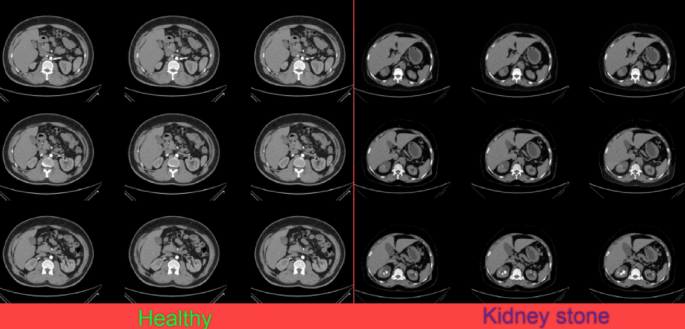

In the current study, to investigate the proposed method, the “CT Kidney Dataset” has been employed. This dataset has been collected by Nazmul Islam and Humaion Kabir31. The CT Kidney Dataset is an archive of different kidney diseases, including healthy (normal), kidney tumors, cysts, stone findings, or which are collected from patients in Bangladesh. Images are in DICOM format, so to utilize in machine learning applications, all of the images have been converted to the JPG format. The dataset includes 10,239 images that is collected from 6775 study cases. All of the images have been marked by a physician to confirm the data accuracy. The dataset includes 12,446 unique data points, with 5,077 normal cases, 2,283 tumor data points, 3,709 cysts, and 1,377 kidney stone cases. This dataset can be downloaded from the Kaggle website31. Figure 1 shows some sample case studies from the CT Kidney Dataset.